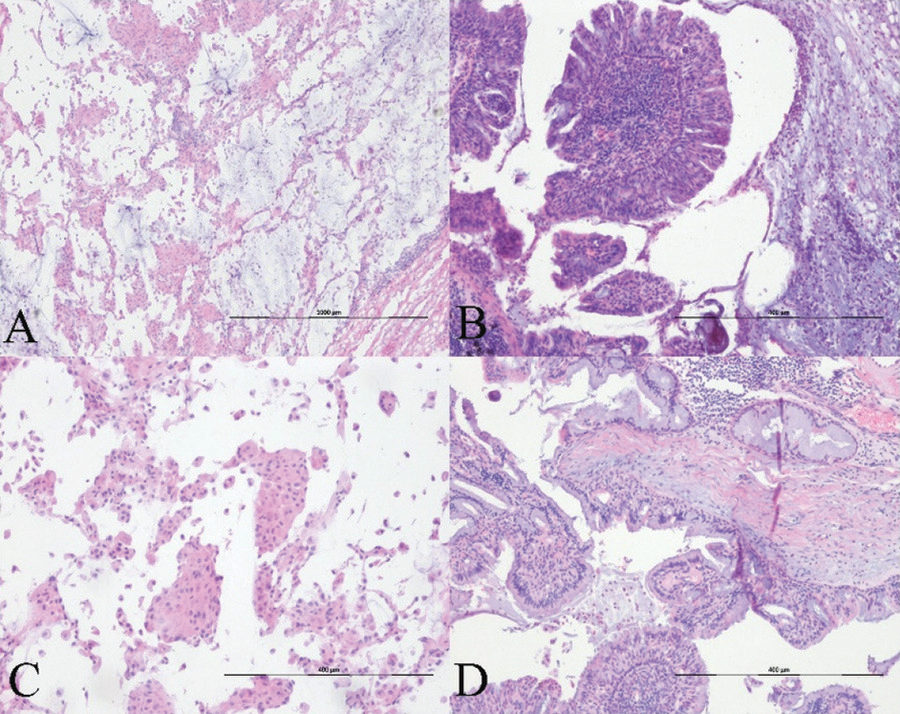

Due to the vascular abutment and peripheral location of the tumor, an image-guided needle biopsy and bronchoscopy were not performed. Additionally, the close proximity to the pulmonary artery and the anticipated risk of significant hemorrhage precluded the possibility of conducting a needle biopsy. Therefore, the right upper lobectomy was performed via video-assisted thoracoscopic surgery. Frozen sections of the lesion showed a well-demarcated mass containing mucus-secreting oncocytes, cuboidal, and columnar cells (Figure 4A–D). The cells in the periphery of the tumor contained mucin and had lepidic growth. No cytologic atypia, mitosis, or necrosis were observed. Moderate stromal inflammation was present. Based on histological findings, the mass was confirmed to be glandular papilloma.

Figure 4

Histopathology. (A–B) Hematoxylin-eosin staining slide images show that the papillary tumor is constituted of pseudostratified columnar epithelium covering the fibrotic core. Surrounding alveolar spaces are filled with mucus on frozen (A, ×40) and permanent sections (B, ×100). (B) The lesion shows multiple papillary fronds lined by stratified and pseudostratified columnar cells. Moderate stromal lymphocytic infiltration and psammoma bodies are noted in the focal peripheral area. (C) In partial areas, small papillae with oncocytic change within the adjacent alveolar spaces are mimicking to the histologic features of the spread through the air spaces of pulmonary adenocarcinoma (×100). (D) Most of the lesion is composed of ciliated or non-ciliated columnar, goblet, and cuboidal cells. There are neither architectural atypia nor cytological atypia (×100).